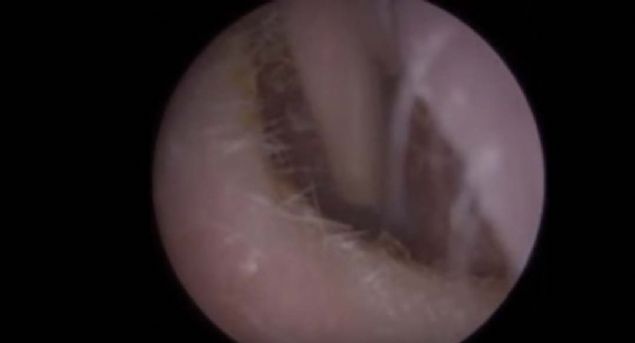

Kolundaki yaranın içinden çıkanlara kimse inanamadı!

Kolunda yara çıkan genç kadın sivilce zannedip önemsemedi ancak gerçek doktora gidince ortaya çıktı.

Yaranın içinden çıkan tropikal bölgede yaşayan ve larvalarını deri altına bırakan botfly cinsi sinekti.

Kolunda yara çıkan genç kadın sivilce zannedip önemsemedi ancak gerçek doktora gidince ortaya çıktı.

İşte o anlar...